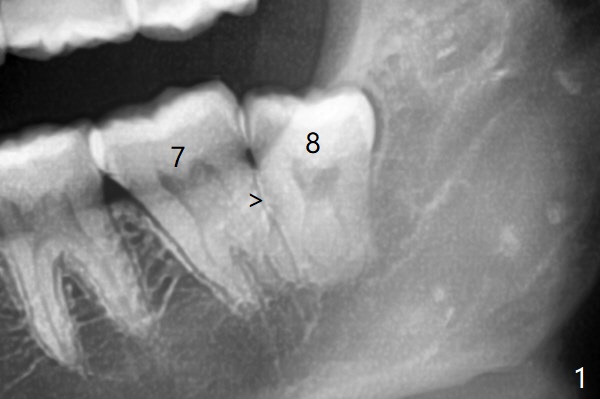

7和8之间只有一层骨皮质(图一:>),8拔除后(图一’),7远中骨质可能退缩,所以植骨尤其重要。医用石膏(Bond Apatite,图二),表面放置1/2胶原塞,4-0 PGA缝合。